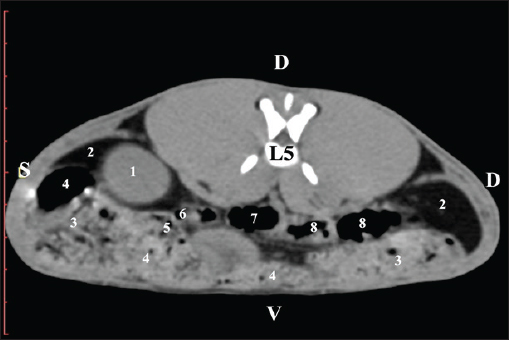

The L5 scan revealed the caudal end of the left kidney. It was adjacent to some small intestinal segments, including the duodenal pars ascendens, ileum, cecum, and colon ascendens (Figs. 12 and 13).

Fig. 12. Pre-contrast computed tomography (CT) anatomical scan of the regio-abdominis media at the cranial L5 edge level. (1) Ren sinister; (2) adipose collections; (3) cecum; (4) colon ascendens; (5) jejunum; (6) pars ascendens of the duodenum; (7) colon transversum; (8) colon descendens.

Fig. 13. Pre-contrast computed tomography (CT) anatomical scan of the regio-abdominis media at the caudal L5 edge level. (1) Ren sinister; (2) adipose collections; (3) cecum; (4) colon ascendens; (5) colon transversum; (6) colon descendens.